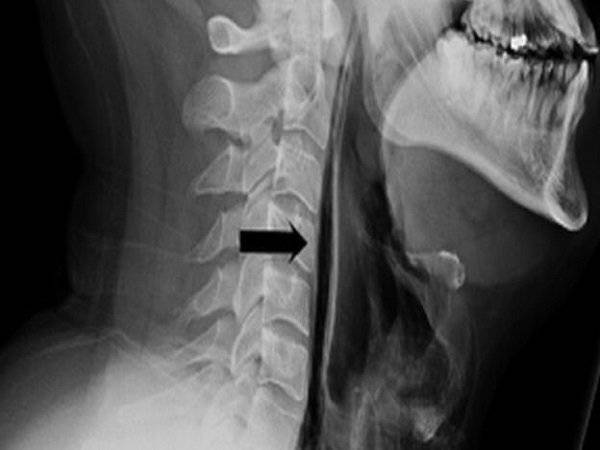

Mới đây các bác sĩ ở Leicester, vương quốc Anh đã điều trị cho một người đàn ông 34 tuổi bị vỡ cổ họng, nguyên nhân là anh ta đã cố gắng kiểm soát một cơn hắt hơi mạnh. Do áp lực của hắt hơi mạnh ngoài tưởng tượng đã làm cho phần ống bên trong cổ họng bị vỡ.

Cổ họng của anh bị tổn thương nghiêm trọng đến nỗi bác sĩ đã lên tiếng cảnh báo tất cả mọi người. Để cố kìm chế cơn hắt hơi, anh đã dùng tay bịt mũi, ngậm miệng. Lực hắt hơi quá mạnh đến nỗi nó đã xé toạc thành một cái lỗ trong cổ họng. Ngay lập tức, cổ sưng phù lên khiến anh không thể nói hoặc nuốt và gần như mất đi giọng nói của mình.

Khi bác sĩ khám, họ phát hiện có tiếng kêu tanh tách khi không khí đi qua cái lỗ mới từ cổ đến xương sườn. Điều này chứng tỏ rằng bong bóng không khí đã tìm đường đi vào sâu trong cơ ngực. Hiện tại, anh được cho ăn qua ống và tiêm kháng sinh tĩnh mạch để phục hồi.